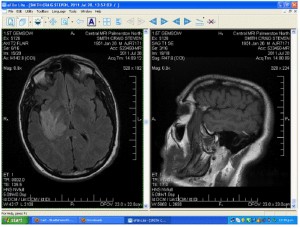

Here is the MRI Scan and some commentary from Craig:

Click on photo for larger image

Looking at the photo on the left hand side:

This is looking up from the bottom of the brain, so the white area left of centre is actually in the Right-hand side of the brain. It is a tumour, some kind of growth. The Dr said it is not an aggressive sort of invasive growth, since it is fairly well-defined. But it is a growth: the fact that it absorbed so quickly the heavy metal they injected into me while this MRI was being done that causes it to appear white proves it is a growth. And its location would explain the symptoms I have: this numbness all down my left side. So what is it? It is not an infection. There is no swelling associated with it. The next step is a full-body CT scan to see if they can pick up any other growth. The assumption there is that another growth in another part of the body might be a primary cancer and this one in the brain could then quite likely be a secondary growth of the same cancer type. Another strategy would be to do a biopsy to find out exactly what it is. Right next to the growth is what looks like an empty space. That’s what it is, with a lobe of the brain to the left of that space. So the growth is actually right there along one surface of the brain, although that surface is behind a brain lobe and quite a distance from the skull. And part of the growth does go quite deep, the Dr said, and is in a rather sensitive part of the brain. So this MRI was done Thursday 28 July and we were told all about it today, Friday. We even have a CD of all these neat images! The neuro surgeons in Wellington also have all this, and the Dr said we could expect to hear from them at any time to inform me of some options or to tell me of their favoured game plan. It has been remarkable and very gratifying to us that everyone has been getting onto the next stage of finding out what this is as fast as you could ever expect. There has been no waiting around for “results.”